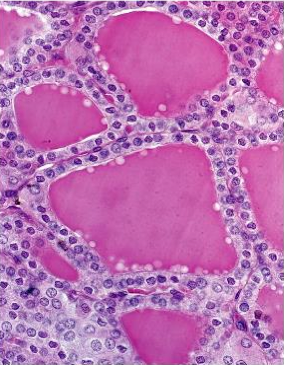

What tissue is this?

Thyroid gland

Colloid

32

Capillary

33

Thyroid follicle

34